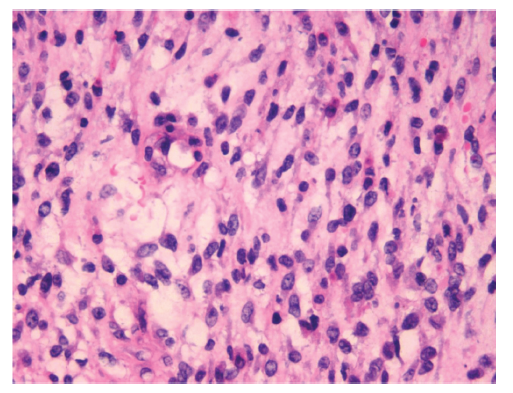

宫颈梭形细胞横纹肌肉瘤一例

A Case Report on Spindle Cell Rhabdomyosarcomas of The Cervix

梭形细胞横纹肌肉瘤是软组织肿瘤的一种,来源于骨骼肌的分化,多见于男性儿童,好发于睾丸旁组织,发生于女性生殖系统的病例罕见。现报道1例中国人民武装警察部队特色医学中心(我院)妇产科2019年收治的宫颈梭形细胞横纹肌肉瘤病例,该患者以绝经后阴道间断出血为首发表现,进展至尿潴留而就诊,临床症状明显,发展迅速,极其罕见,但尚无特定有效的治疗方式。现回顾分析该病例特点,以期提高妇产科医生对该病的认识。

As one of soft tissue tumors, spindle cell rhabdomyosarcoma originates from the differentiation of skeletal muscle, which is more common in male children, especially often occurs in paratesticular tissue and rarely occur in female reproductive system. Now, a clinical case on a woman diagnosed with spindle cell rhabdomyosarcoma of the cervix who were hospitalized in the Department of Obstetrics and Gynecology, the Characteristic Medicine Center of the Chinese People′s Armed Police Forces in 2019 is reported. This patient was the first manifestation of postmenopausal bleeding and has developed to urinary retention. The disease developed rapidly and was extremely rare with obvious clinical symptoms, but there was no specific effective treatment. We hope to share the case report in order to improve the academic vision and enhance the understanding of the disease in obstetricians and gynecologists.